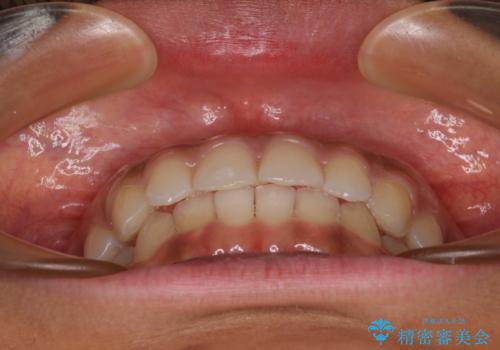

- 上下前歯の叢生を気にして来院された患者様です。

インビザラインでの治療を希望されていて、デコボコの程度が中等度であり、安価なパッケージにて対応可能と判断されたため、インビザライン・モデレートを用いて矯正治療を行うこととしました。

インビザライン・モデレートは、製作できるアライナーの枚数に制限があるため、移動可能な量に限りがあるものの、インビザライン・ライトよりも枚数が多いため、幅広い症例に対応可能です。